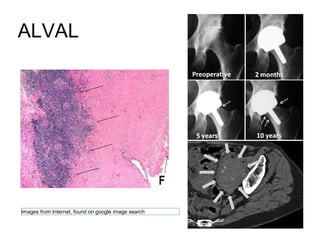

Effect of increased metal ions

• Carcinogenesis, metal sensitivity and

organ toxicity

• Locally unusual lymphocytic

aggregates called acute lymphocytic

vasculitis associated lesions (ALVAL)

or pseudotumour are seen

ALVAL

Images from Internet, found on google image search